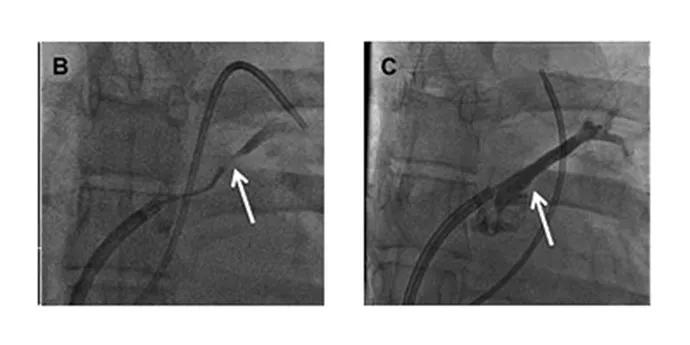

An angiogram of the left atrium demonstrated subtotal occlusion of the LSPV (Figure B). A wire was passed through the occlusion into the LSPV branches. A drug-eluting stent was then placed in the ostium of the LSPV, yielding complete patency of the vessel (Figure C).

Figures B and C. Angiograms of the left atrium demonstrating subtotal occlusion of the left superior pulmonary vein (B) and complete vessel patency following placement of a drug-eluting stent in the ostium of the left superior pulmonary vein (C).